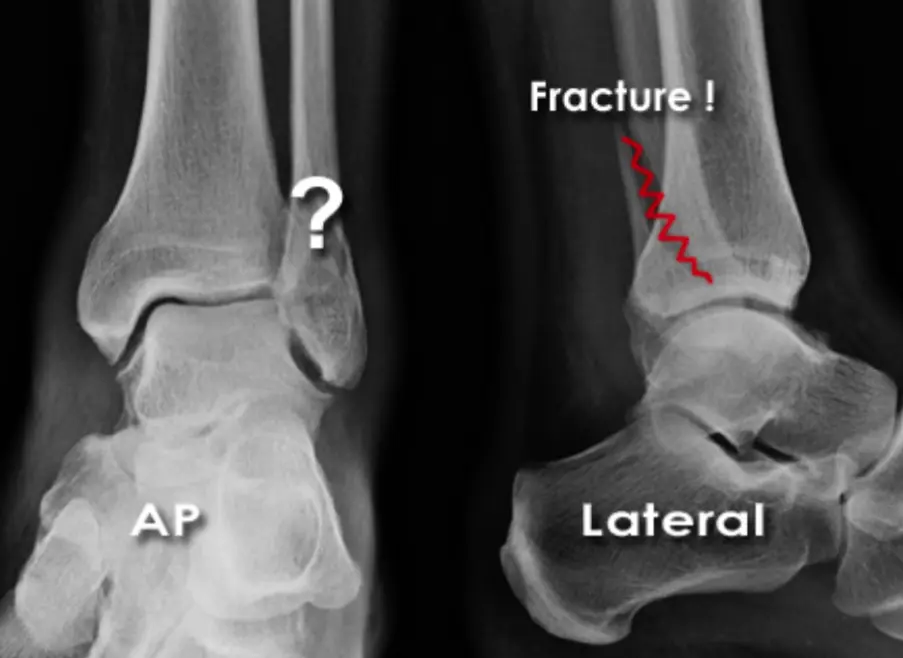

Patient â 40âyearâold female

Mechanism â Jumped from the 2nd floor

Presentation â Pain and swelling around the right knee

Site â Lateral tibial plateau

Type â Simple

Fracture line â Vertical split

Intraâarticular â Yes

Displacements â Small gap in the articular surface

Special issues â Requires surgery for absolute stability

A 32âyearâold patient fell from a palm tree and now presents with pain and swelling around the left knee.

- Site: Lateral tibial plateau

- Fracture type: Comminuted

- Fracture line: Vertical split

- Displacement: Depressed

- Special issues: CT scan required for detailed assessment

- Management needed: Surgical intervention